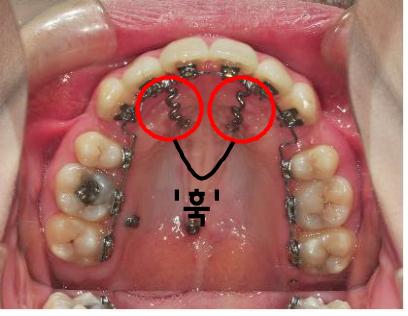

와이어를 연결하면서 하나 더 새로운 장치를 부착했어요~

바로 ‘훅’이라는 장치인데요, 이 장치의 역할은 저의 치아치료에서는

앞니쪽부분을 들어올리는 역할을 하게 될 거라구 하셨어요~

그래서 ‘훅’을 이용해 앞니를 올리는 치료를 하였습니다.

지금도 잘 부착되어있구요~ 저는 잇몸을 눌러 아프면 어쩌나했는데,

선생님께서 섬세히 치료해주신 덕분인지 있는지도 모를 정도로 아픈건 전혀없네요^^